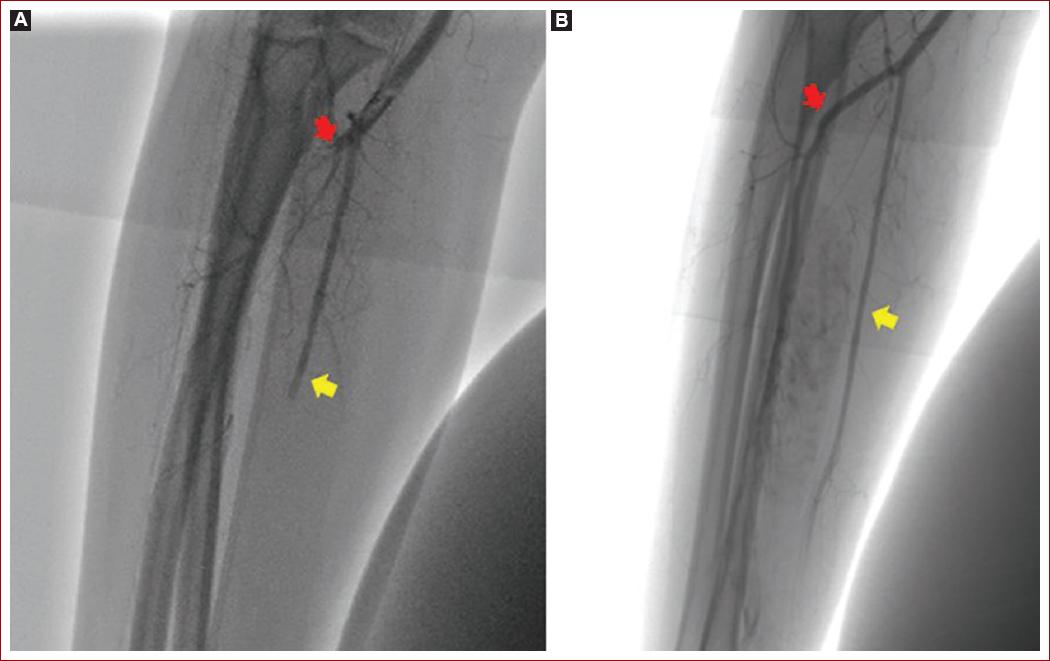

Durante la estancia en unidad de cuidado intermedio se evidencia progresión de cianosis y frialdad de la extremidad, con llenado capilar mayor a 5 segundos, por esto es revalorada por cirugía vascular, confirmando progresión de la lesión, con aparición de zonas de necrosis en regiones subungueales, razón por la cual se realiza de urgencia arteriografía periférica + trombectomía (Figs. 1B y 1C). Durante el procedimiento quirúrgico se evidencia a nivel de la primera porción de la arteria subclavia presencia de lesión trombótica oclusiva del 70% con alto riesgo embolígeno (Fig. 2A), por lo que se procede a realizar trombectomía con sistema Solent de Angiojet. Sin embargo persiste con estenosis residual de más del 30% por un coágulo crónico, por lo que se decide fijar con un stent de nitinol 8 x 60 para disminuir el riesgo embólico (Fig. 2B). Igualmente, a nivel distal de la arteria braquial se evidencia oclusión del 90% con ausencia de flujo a arteria cubital, radial e interóseas (Fig. 3A), por lo que se realiza trombectomía más paso de balón de angioplastia de 3A a largo de la arteria radial, logrando recanalización completa (Fig. 3B).

Figura 3 Arteriografía periférica vasos infracondilios + trombectomía. A: oclusión completa de arteria radial (flecha roja) y cubital (flecha amarilla). B: recuperación de flujo arterial en arteria radial (flecha roja) y cubital (flecha amarilla) posterior a trombectomía percutánea.